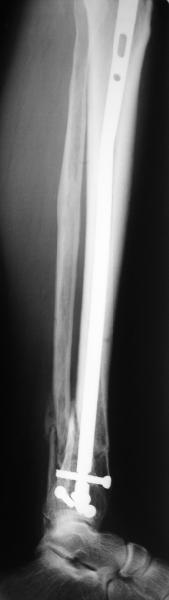

Направили к нам пациентку 35 лет с переломом дистального отдела костей голени.

У нас сделали снимок сзахватом обоих суставов - еще и проксимальный метафиз сломан. Чем бы у вас фиксировали такой перелом? Как его правильно закодировать по классификации АО?

Сделали все-таки стержнем. На всякий случай просверлил дополнительное проксимальное отверстие, так что получилось три 45-градусных винта.

В дистракторе провеи спиц поболше в прокисмальном отделе, чтобы не разобщить фрагменты при сгибании колена. Комментарии и критика приветствуются.

We proceeded with nailing using a small wire distractor, with few wires at the proximal end to prevent displacement with forced knee flexion. Images attached. Comments and critics are welcome.